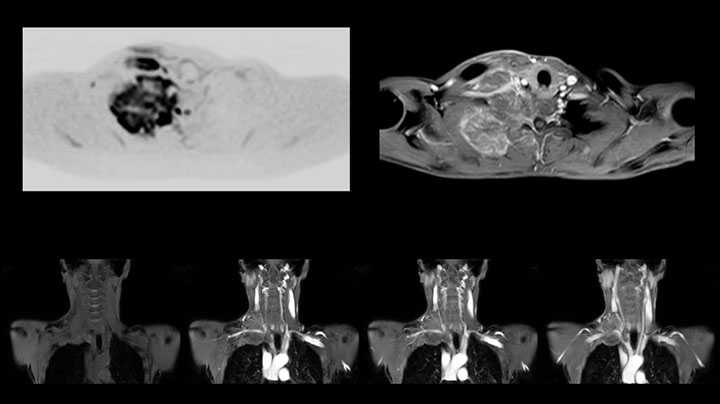

MRI of Pancoast tumor

Although the area between the neck and the top of the lung is one of the most difficult areas for MRI, Prodiva 1.5T images show good quality in this 56-year-old male with Pancoast tumor on the right. mDIXON TFE images shows excellent fat suppression in the neck area and the DWI shows almost no distortion.

MRI of Pancoast tumor

Although the area between the neck and the top of the lung is one of the most difficult areas for MRI, Prodiva 1.5T images show good quality in this 56-year-old male with Pancoast tumor on the right. mDIXON TFE images shows excellent fat suppression in the neck area and the DWI shows almost no distortion.